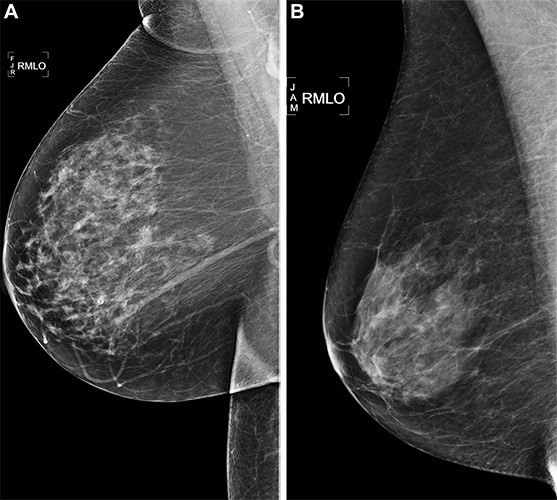

Right medial lateral oblique (RMLO) screening mammograms show negative results from 2016 in (A) a 73-year-old woman with Mirai artificial intelligence (AI) risk score with more than 90th percentile risk who developed right breast cancer in 2021 at 5 years of follow-up and (B) a 73-year-old woman with Mirai AI risk score with less than 10th percentile risk who did not develop cancer at 5 years after 5 years of follow-up. Image Credit: https://doi.org/10.1148/radiol.222733 ©RSNA 2023